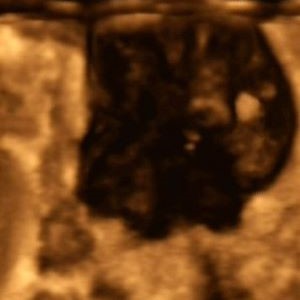

Eine erste Untersuchung ergab einen suspekten Tastbefund an der linken Brust. Die folgende Sonografie einen Tumor; Verdacht auf Malignon (Abb. 1, 2). Die durchgeführte Duplex- (Abb. 3) und 3D-Songrafie (Abb. 4) sowie die Elastografie (Abb. 5) erhärtete die Verdachtsdiagnose.

Abb. 3

Abb. 4